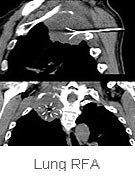

Cancers (lung, liver,

RFA is an excellent method of treatment

for liver, lung and renal tumors.

In

the lung, RFA is indicated in all situations where

surgery would be indicated, but is not being performed

due to either other co-morbid conditions that would

make surgery risky or when the patient refuses. It

is also performed when surgery is not the method of

choice, to supplement radiotherapy or chemotherapy

for associated metastatic disease.